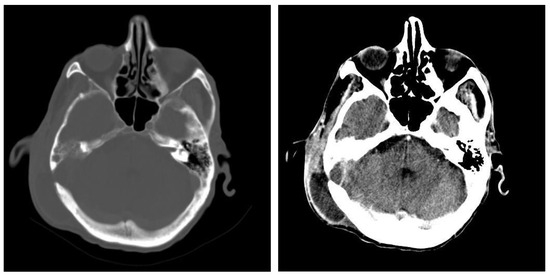

3.1.2. Computed Tomography and Magnetic Resonance Imaging

| CT Aspects | Number of Patients | Percentage |

|---|---|---|

| Fluid accumulation | 168 | 100% |

| Osteolysis | 152 | 90.47% |

| Osteocondensations | 128 | 76.19% |

| Cholesteatoma | 48 | 28.57% |

| Exocranial extensions | 48 | 28.57% |

| Intracranial extensions | 24 | 14.28% |

| Changes to the external auditory canal | 68 | 40.47% |

| Ossicular chain damage | 144 | 85.71% |

| MRI Aspects | Number of Patients | Percentage |

| Edema | 128 | 100% |

| Cholesteatoma | 40 | 31.25% |

| Exocranial extensions | 40 | 31.25% |

| Intracranial extensions | 32 | 25% |

| Inner ear damage | 20 | 15.62% |